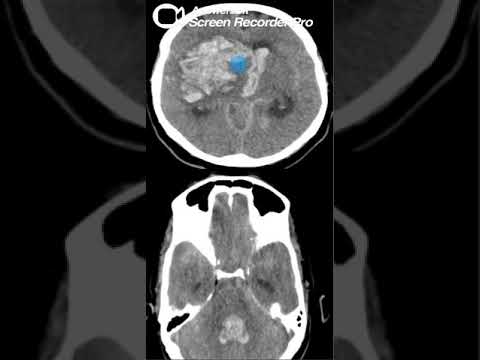

Video: Quiz in English case 17

Video oleh Dr Hazem Hamed Radiology channel